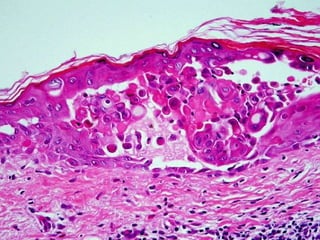

microscopic, acantholysis

Epidermis/Dermis, bullae, pemphigus

BULLOUS DISEASES •PEMPHIGUS(VULGARIS) • • • • BULLOUS PEMPHIGOID DERMATITISHERPETIFORMIS EPIDERMOLYSIS BULLOSA PORPHYRIA • “ACANTHOLYSIS” is the common unifying finding, as is basement membrane immunoglobulins

• #88 Acantholysis in the bullous family of diseases. Notice that the “seperation” can be within the acanthocytes, i.e., the stratum spinosum, or at the dermal-epidermal junction. So would you imagine many of the bullous disorders are diseases of basement membrane and tonofibrils (i.e., desmosomes), and may be autoimmune?